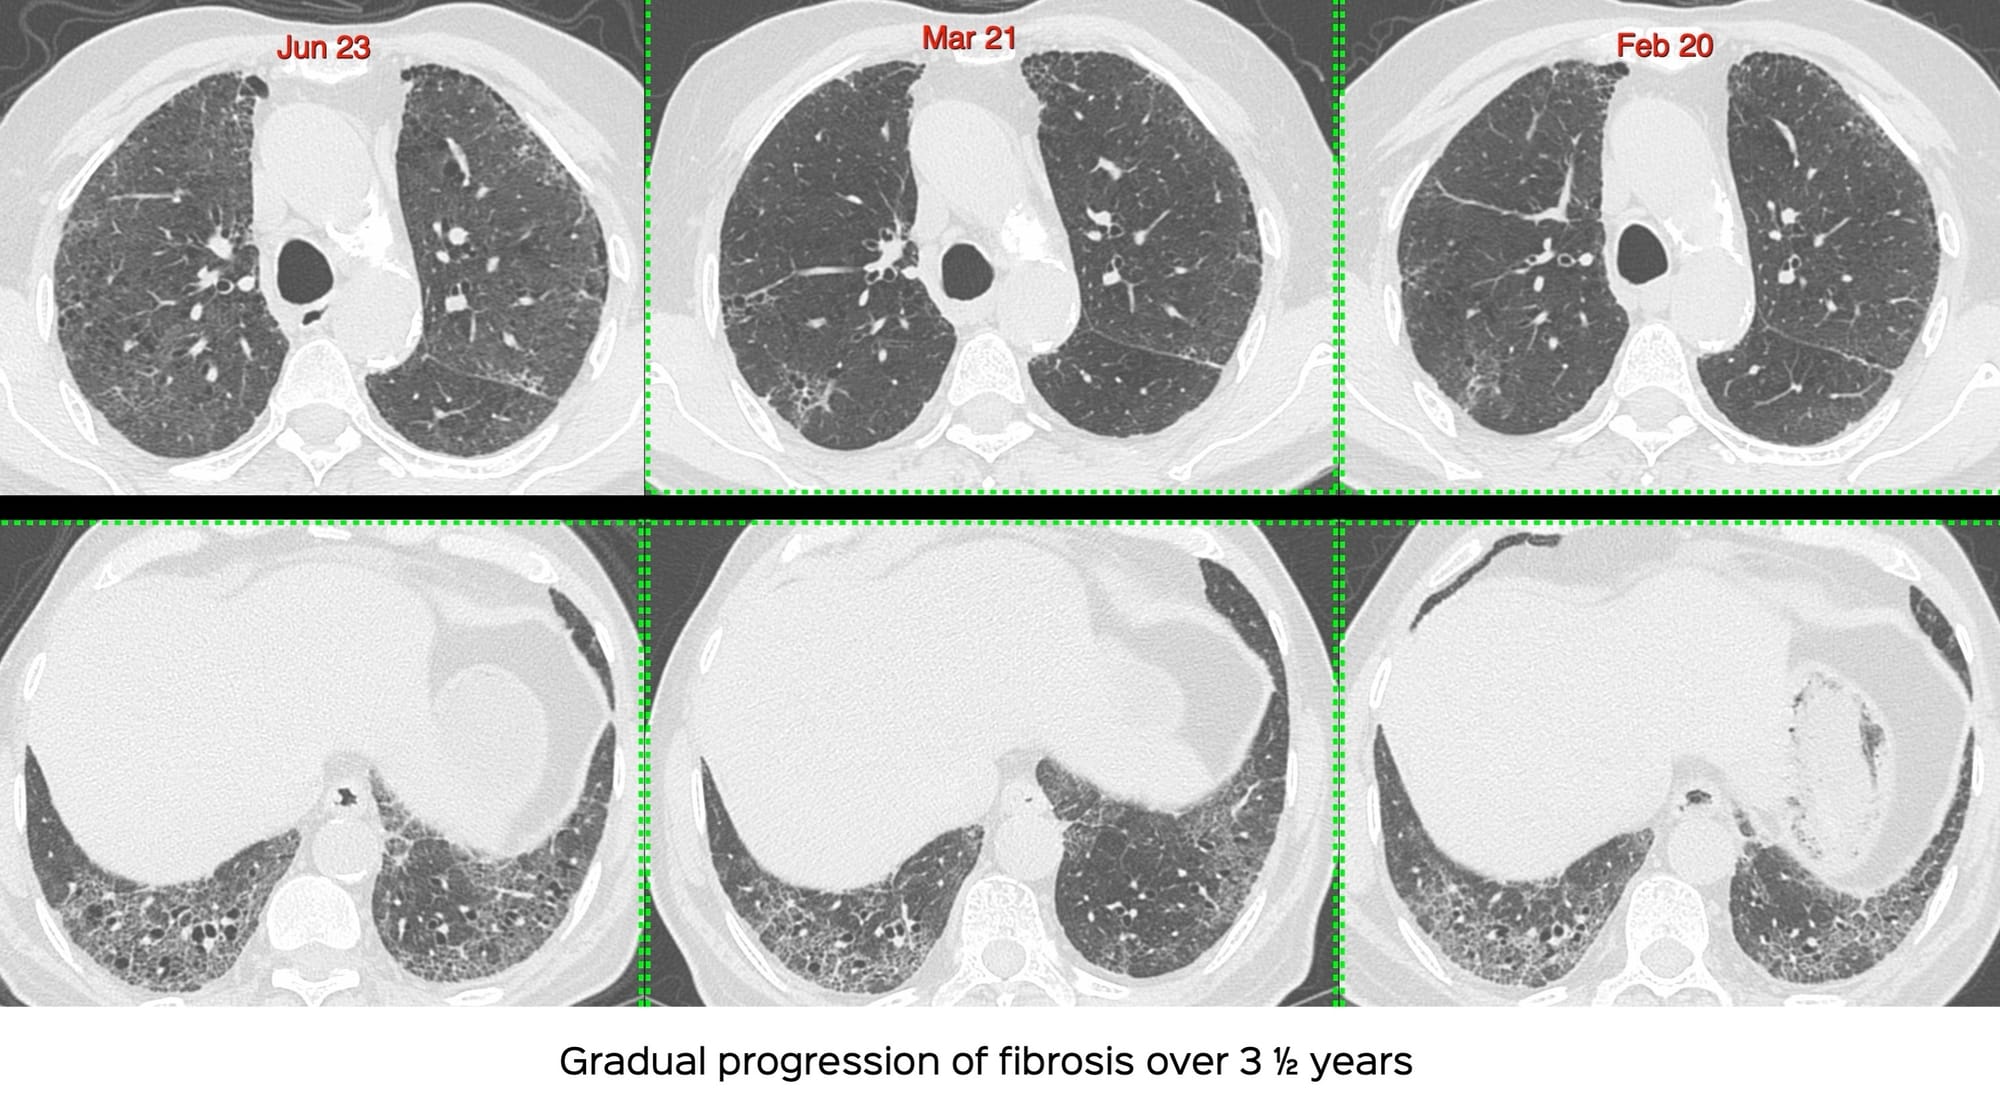

A 69-years old ex-smoker presented with breathlessness in 2020.

He had UIP/IPF.

He progressed over the next 3 years.

One day in 2024, he presented with acute increased dyspnea.